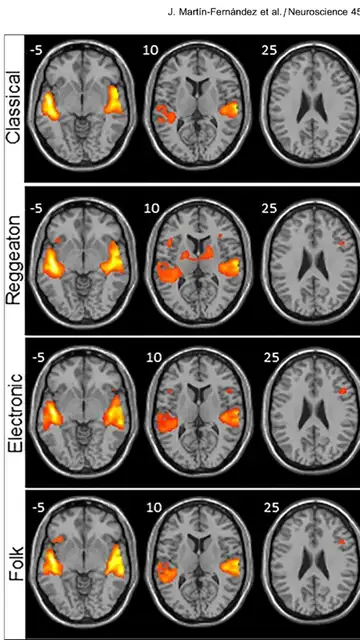

Los investigadores analizaron anatómicamente el cerebro de cada participante y luego la señal BOLD, que muestra qué áreas del cerebro reclutan oxígeno (lo que sucede cuando se activan), y a través de un software se representaron con diferentes colores según se activasen más o menos.

Concluyeron que el reguetón fue el estilo que mostró mayor activación en las regiones del cerebro encargadas de procesar los sonidos (áreas auditivas) y el movimiento (áreas motoras), unas diferencias que resultaron mayores en comparación con la música clásica. La electrónica también mostró una mayor activación de las regiones motoras, pero significativamente menor que el reguetón.